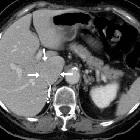

Isolated

intracaval recurrence of resected renal carcinoma. Follow-up contrast-enhanced CT after sunitinib therapy showed dramatic size decrease of tumor thrombosis (a, b) at six months (arrows) and only a small filling defect (c, d) at three years (arrows).